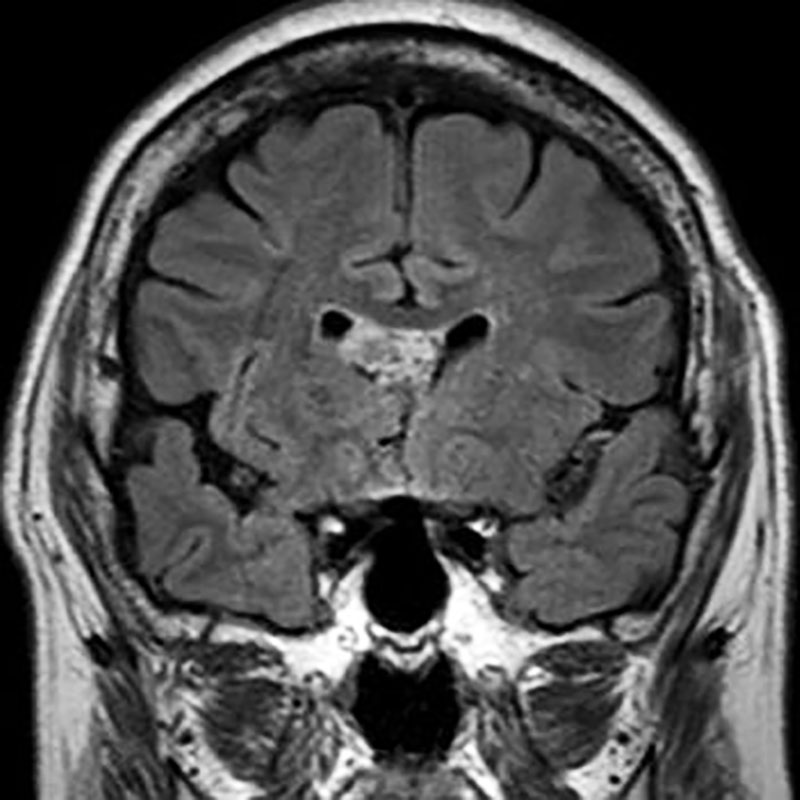

345

'22年11月

70代

頭蓋底腫瘍

頭蓋内腫瘍摘出術

No.’22_102 手術前1

No.’22_102 手術前2